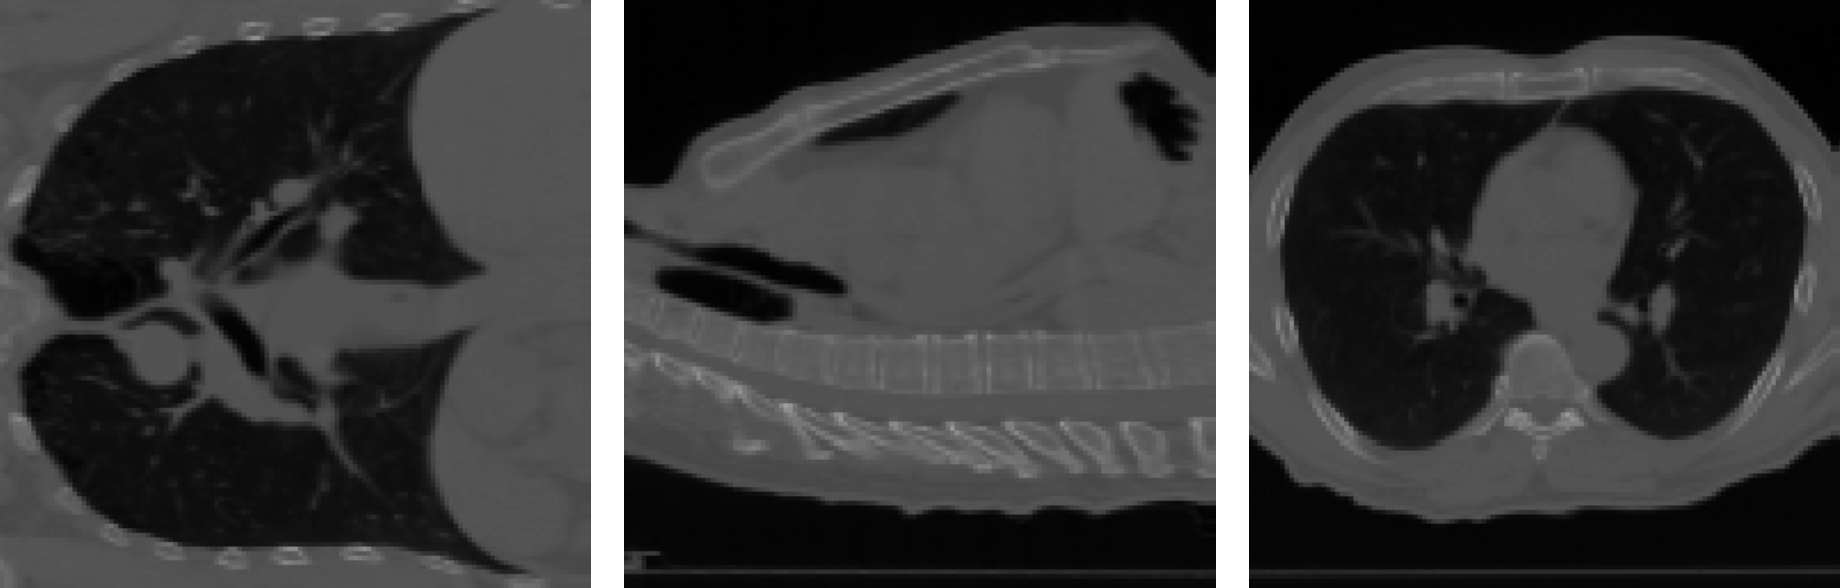

In this section, we show the capability of the proposed three formulations in Section 3.2.4 in real data. The 4DCT dataset, consisting of two lung CT scans featuring 300300 pairs of landmarks, is chosen for demonstration. This dataset can be accessed through the Deformable Image Registration Laboratory (www.dir-lab.com).

Following ZhangDaoping2022AUFf , we resized the images to 1283128^{3} and normalized the pixel values to the range [0,1][0,1]. Unless otherwise specified, we empirically selected α1=0.01\alpha_{1}=0.01, α2=50\alpha_{2}=50, α3=1\alpha_{3}=1, α4=0\alpha_{4}=0, α5=500\alpha_{5}=500, and α6=500\alpha_{6}=500 in (18). In Fig. 7, we present snapshots of the resulting 3D mappings, along with the histograms of detfθ\det\nabla f_{\theta} and the training losses for various variational models. From Fig. 7 and Table 3, we make the following observations:

Additionally, Fig. 8 displays various slice views of the source image SS, target image TT, warped image SfθS\circ f_{\theta}, and their respective absolute differences. These results highlight the effectiveness of incorporating intensity information into our framework.

Figure 8: The 4DCT Lung CT example. Visualization of the registration results via three slice views, i.e., x=0.5,y=0.5,z=0.5x=0.5,\,y=0.5,\,z=0.5. (a)-(b) Three views (slices) of the source image SS and target image TT, respectively. (c) Three views of the absolute difference between SS and TT. (d)-(e) The landmark matching registration results. (f)-(g) The intensity matching registration results. (h)-(i) The hybrid matching registration results.